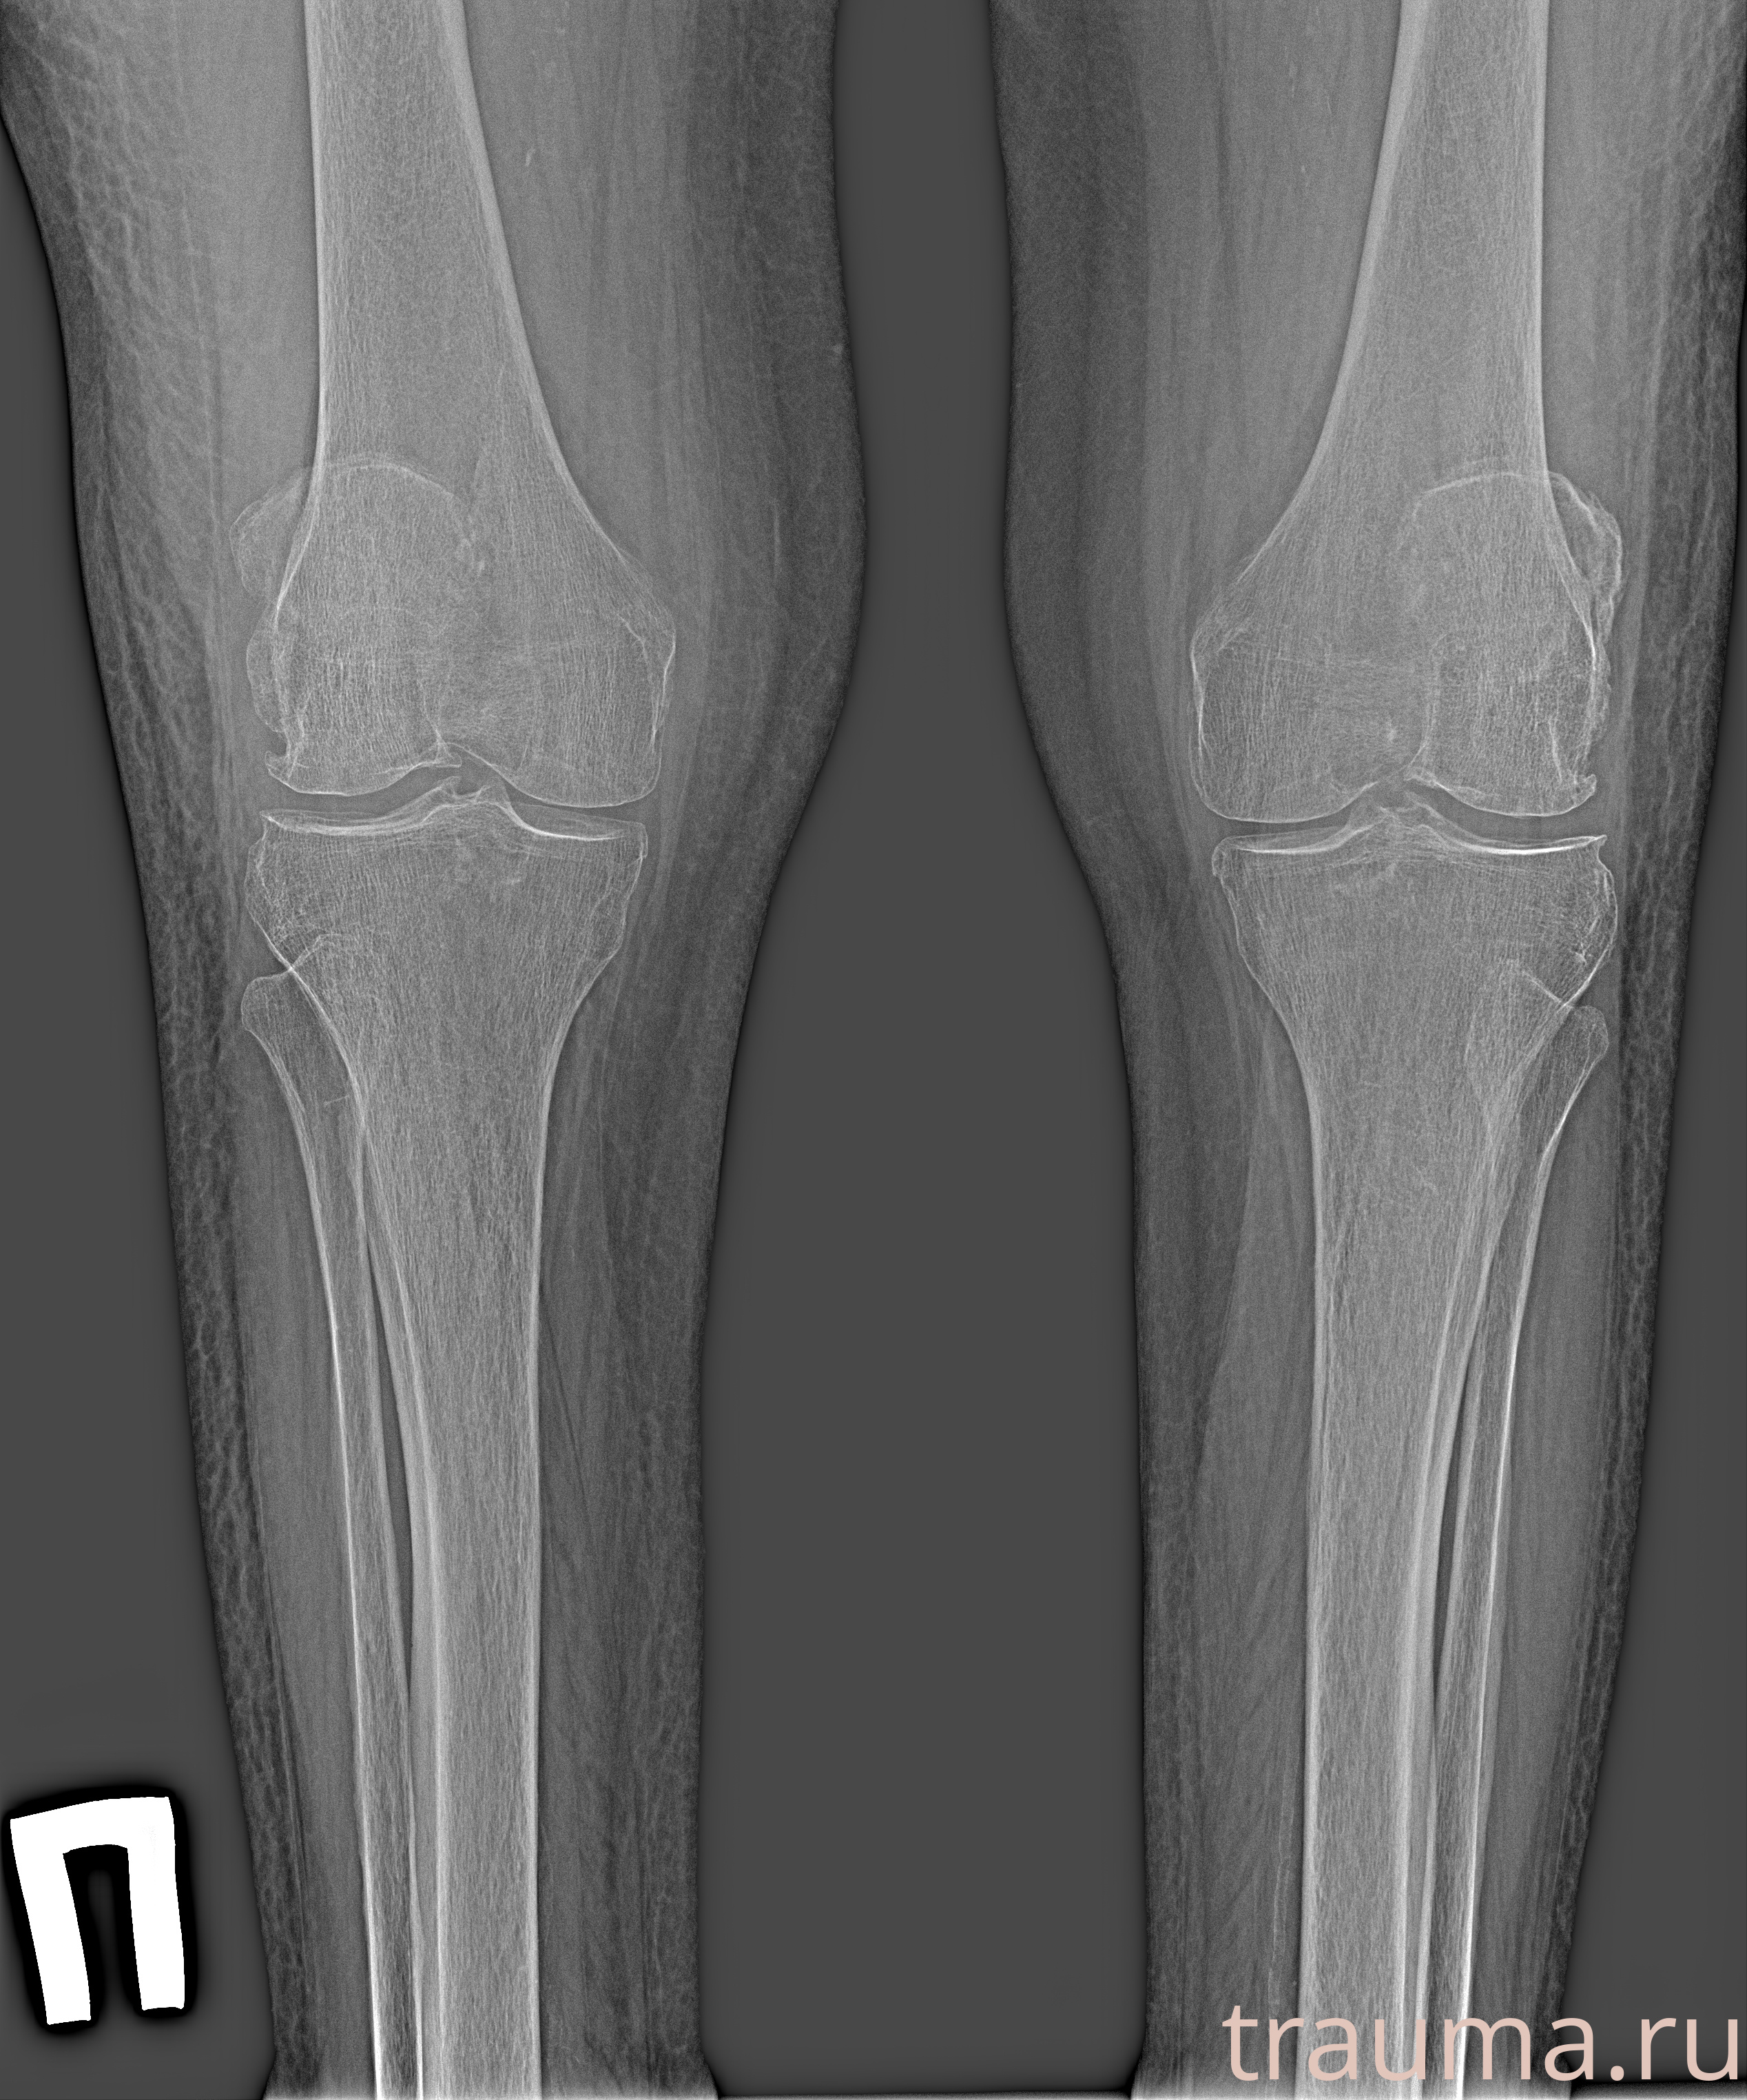

Рентген на дому: по вашему адресу приезжает врач-рентгенолог, травматолог-ортопед с мобильным рентгеновским аппаратом, проводит диагностику травмы или заболевания, делает необходимые рентгенограммы, дает рекомендации по дальнейшему лечению. Получить качественные снимки в домашних условиях возможно благодаря уникальной методике, разработанной МосРентген Центром для института  Склифосовского